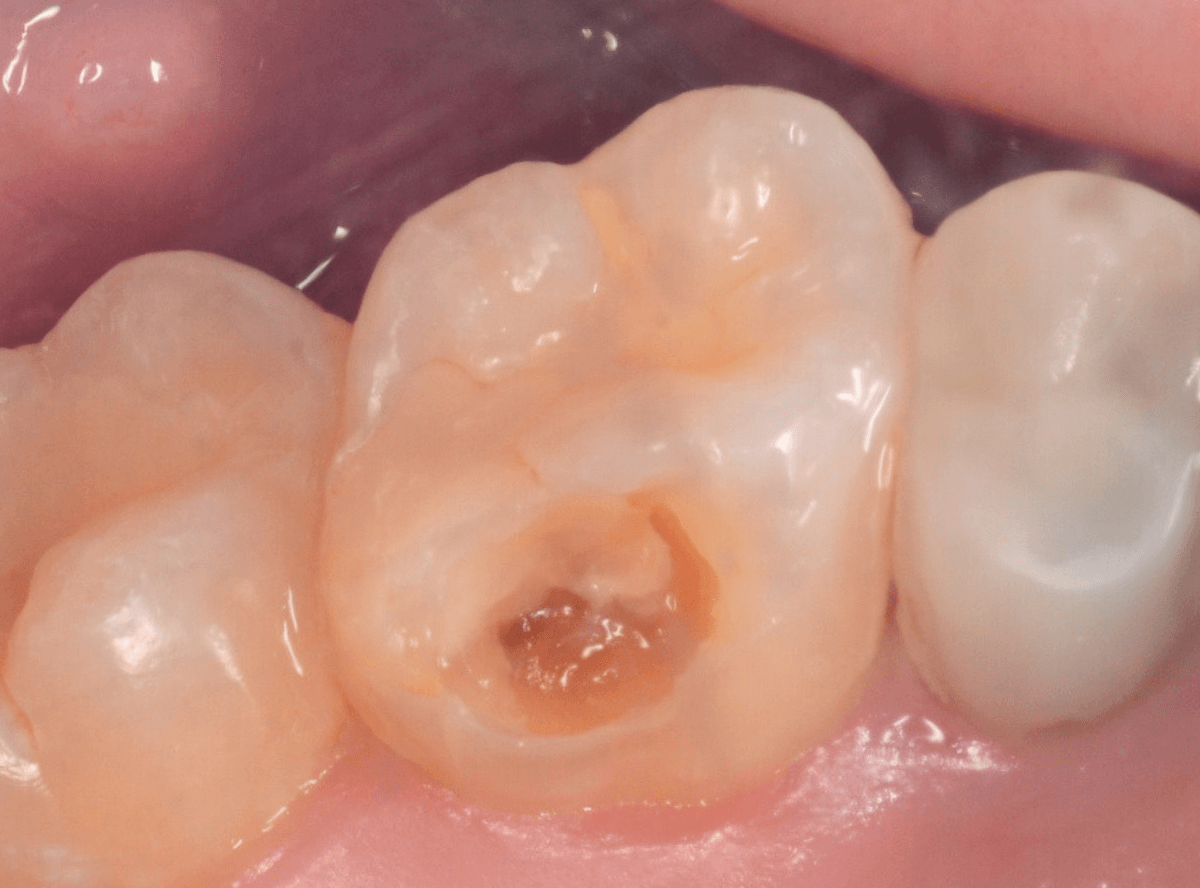

Case.20 劣化したレジン側面から進行した虫歯

「つめものが欠けたまま長期間放置して、歯がしみる」という訴えで来院された患者さんさんです。

拝見すると、劣化したレジンが欠けて、中で虫歯になっているのがわかります。

・欠けたまま長期間放置した

・しみるという自覚症状がある

事から、中で深い虫歯になっている事が想像されます。

レントゲン写真で確認します。

このように、初見では虫歯になっている事が明らかなのに、レントゲン写真ではまったくわからないとう事もあります。

レジンを外しながら、虫歯を確認します。

慎重にレジンを除去しましたが、途中で露髄(神経が露出する事)しました。

歯の神経の中には、血管も含まれているので、神経が露出すると、このように出血します。

「しみる、痛い」などの明確な強い症状がある場合、このような状況の事が多いです。